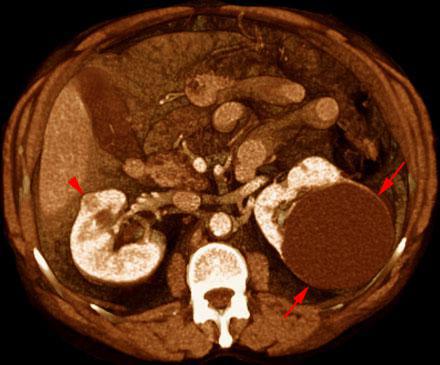

Hipernefroma 2